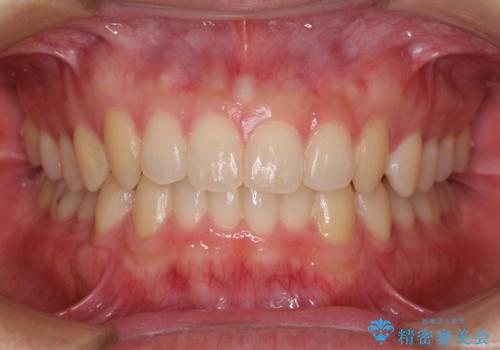

前歯のデコボコをインビザラインで改善

- 前歯のデコボコや八重歯の様になっていることを気にして来院された患者様です。

犬歯捻れて前方に飛び出しており、下顎前歯もそれに沿うようにデコボコとなっていました。

IPR(歯と歯の間を削る処置)によりスペースを獲得して上下顎前歯のデコボコを改善し、前歯が前方に突出しないように設定した上で、インビザラインにて矯正治療を行うこととしました。

途中体調を崩され、長い期間矯正治療を休むことになったため4年半ほどの治療期間がかかりました。